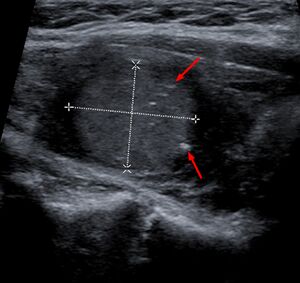

سرطان الغدة الدرقية اللبي على الموجات فوق الصوتية مع تكلسات صغيرة نموذجية (الأسهم)

يتم التشخيص بشكل أساسي عن طريق الشفط بالإبرة الدقيقة لآفة الغدة الدرقية لتمييزها عن الأنواع الأخرى من آفات الغدة الدرقية.[6] سيظهر الفحص المجهري سدى نشواني مع تضخم في الخلايا المجاورة للجريب.